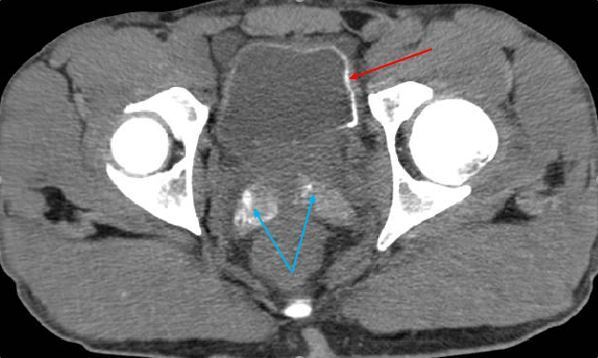

Devant un tableau clinique évocateur de colique néphrétique, avec une hématurie retrouvée à la bandelette urinaire, un scanner abdominal sans injection est réalisé. L’examen ne retrouve pas de lithiase au niveau des voies excrétrices rénales mais une ectasie calcifiée de l'uretère prévésicale gauche ainsi qu’une calcification diffuse de la paroi vésicale et des vésicules séminales (fig. 1).